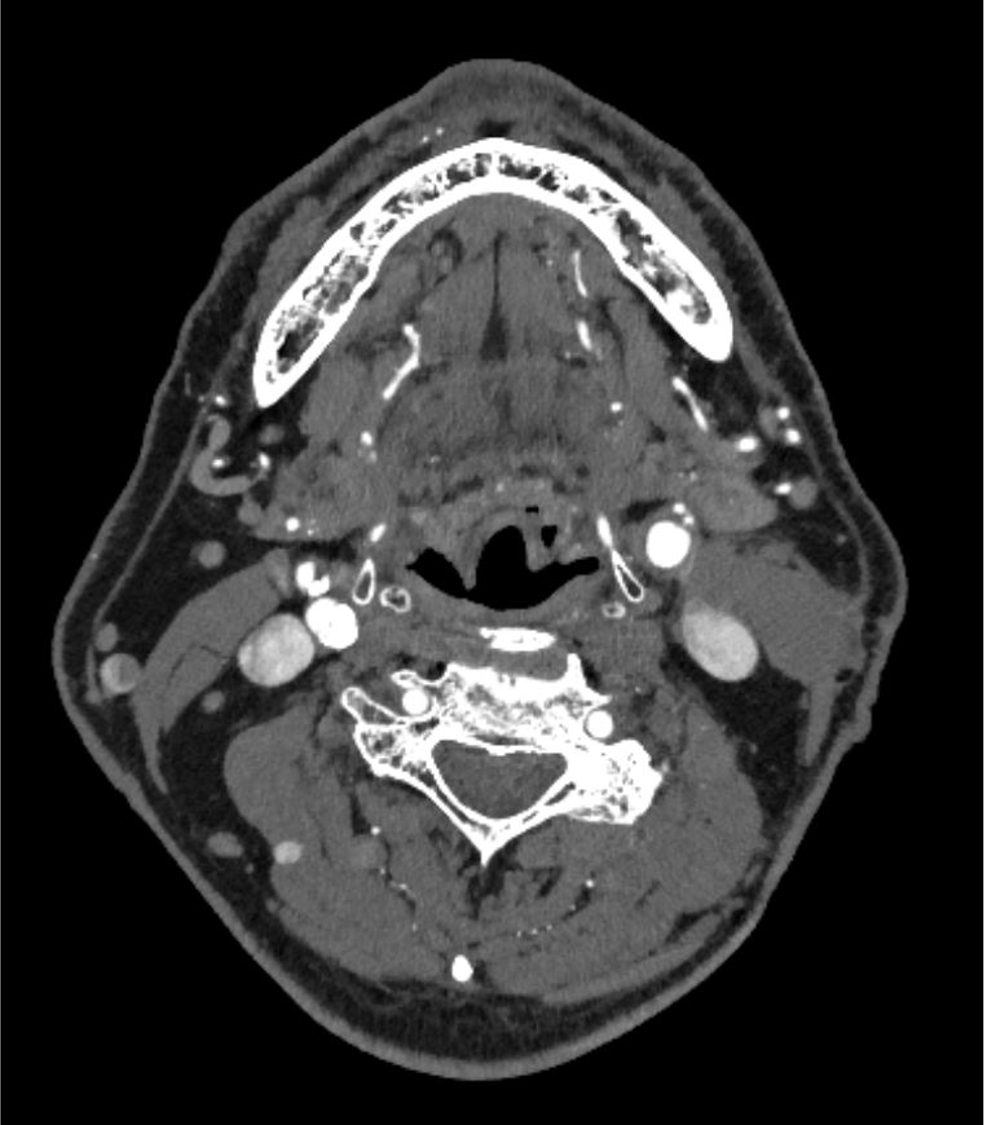

70歳代、男性、52kg、内頸動脈狭窄

右内頸動脈狭窄症の術前評価

2年前に左内頸動脈狭窄症に対して内膜剥離術施行後。今回、右内頸動脈狭窄の進行が疑われ、術前精査のためCT angiography施行。

内頸動脈狭窄症において、造影CTはMRIと並んで必須の検査である。MRIが苦手とする石灰化の評価、薄いスライス厚での狭窄率評価が、造影CTでは行いやすい。動脈相での評価が望ましく、血管内と血管外の境界が可能な限りシャープである方が、狭窄率の評価が行いやすい。

Virtual Monoenergetic Imageで高エネルギー側の表示をすることで、金属アーチファクトを低減できたり、今回の症例のように、Iodine mapを用いることでヨード濃度を推定することができたり、Purelumen画像でCaなどの石灰化を除去することで、内腔の表示をより明瞭化する技術がある。シャープネスの高い動脈相の画像が望ましく、ヨード量は600mgI/kgは維持できるように気をつけている。